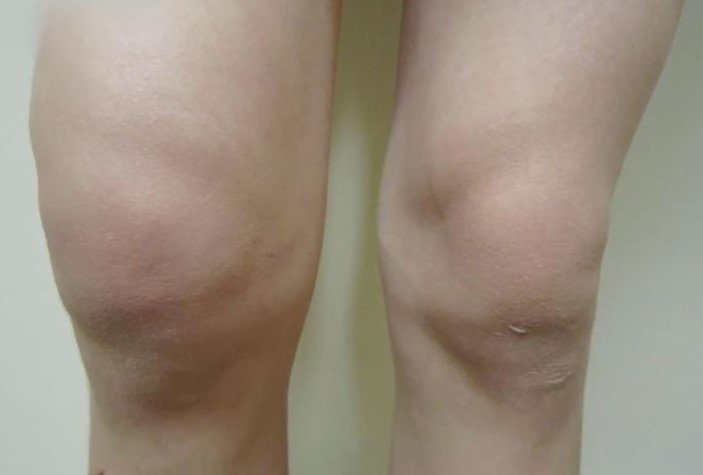

- تورّم سريع خلال ساعات: تجمع سائل أو دم داخل مفصل الركبة يسبب تورّمًا ملحوظًا خلال فترة قصيرة.